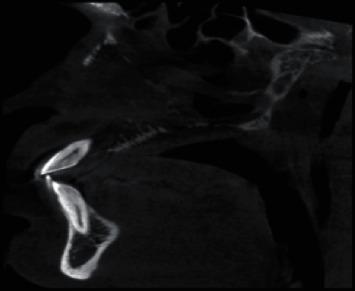

Polymorphous low-grade adenocarcinoma (PLGA) is a slow growing malignant tumor of minor salivary glands and is generally of indolent nature. However, according to the most recent WHO Classification of Salivary Gland Tumors (2017), the cancer is classified as Polymorphous AdenoCarcinoma (PAC). PAC presents as a less aggressive tumor, though it could on rare occasions demonstrate distant metastasis. . A 47-year-old man who was referred by a private practitioner for a CBCT scan in reference to a proliferative soft-tissue growth in the hard palate. The growth was mild and tender and there was Grade III mobility in relation to all the maxillary teeth. Panoramic radiograph taken previously had revealed evidence of alveolar bone loss in relation to the maxillary teeth and was inconclusive of any other findings. The CBCT scan revealed evidence of moth-eaten appearance of maxilla with destruction of medial and lateral walls and floor of maxillary sinus. There was also evidence of involvement of right eustachian tube, ethmoidal wall, and nasopalatine canal. An intraosseous malignancy of the palate was suspected, and a total maxillectomy was performed. The tissue sample was sent for histopathological assessment wherein changes diagnostic for polymorphous low-grade adenocarcinoma of the palate were observed.